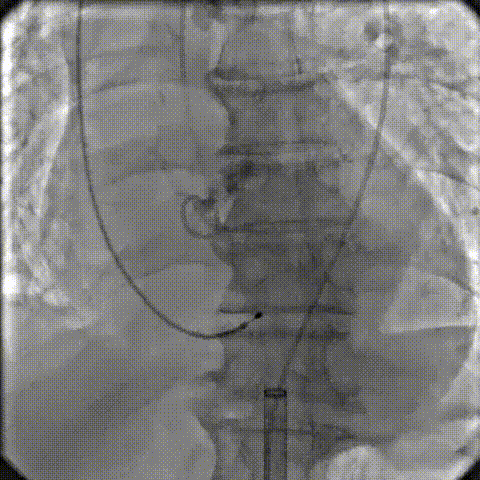

术中剪影